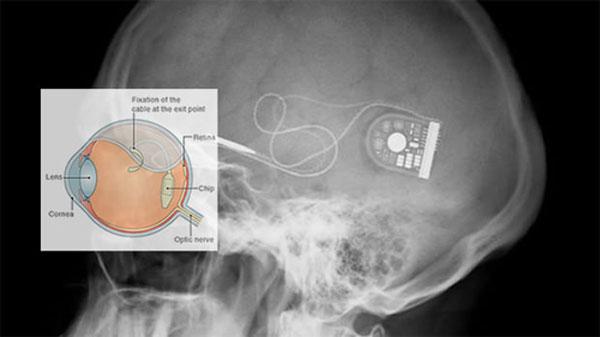

Cấy ghép một cảm biến ảnh vào sau võng mạc của bệnh nhân.

Điểm mấu chốt ở sự chuyển biến thần kỳ này là một cảm biến hình ảnh có diện tích chỉ 3 x 3 mm có 1.500 điểm ảnh nhạy sáng đóng vai trò tiếp nhận ánh sáng và các tế bào hình nón. Các phẫu thuật sau đó đã đặt thiết bị này phía sau võng mạc và kết nối với thần kinh thị giác của bệnh nhân đồng thời cấy ghép một chip điều khiển đằng sau tai của họ. Các cảm biến, được phát triển bởi một công ty của Đức mang tên Retina Implant AG sau đó sẽ gửi tín hiệu đến các dây thần kinh thị giác và đến não mỗi khi nó phát hiện ánh sáng.